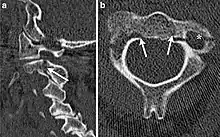

كسور الفقرات العنقية

- كسر جيفرسون.[3]

- خلع فهقي محوري (بالانجليزية: Atlanto-axial subluxation)

- كسر هانغمان (بالانجليزية: Hangman's fracture)

- كسر الفائق (الناتئ السني) للمحور.

- مفصل وجيهي قافز (أحادي أو ثنائي الجانب)

- كسور الفقرات العنقية غير المحورية.

- الكسور القلعية.

- كسر الدمعة.